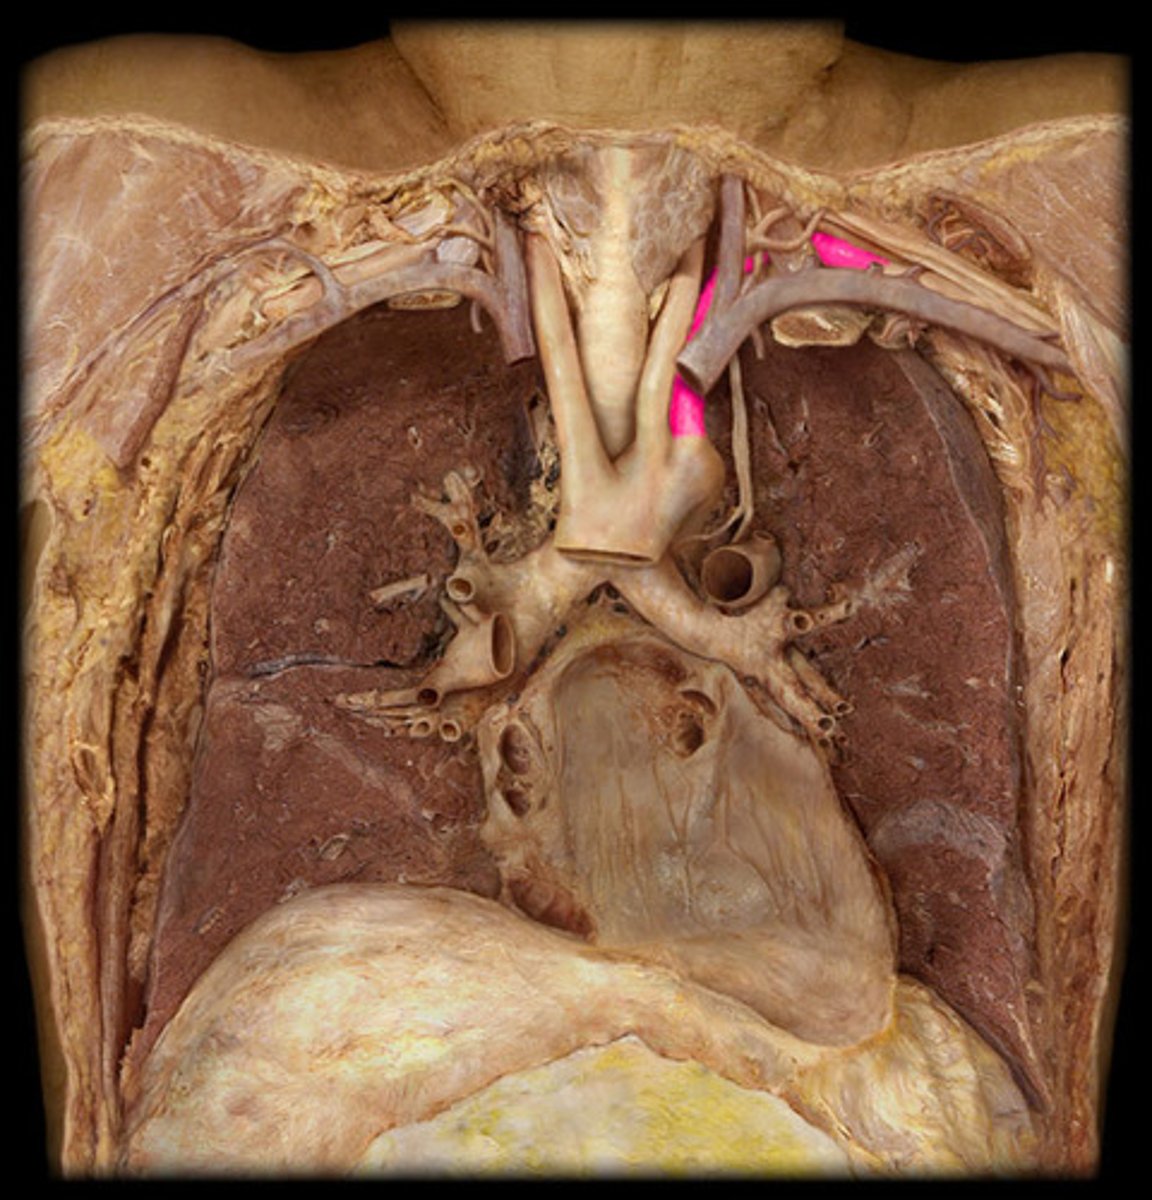

L. common carotid artery

second branch off the aortic arch

L. subclavian artery

third branch of the aortic arch

L. internal thoracic artery

comes off the l. subclavian, going towards the thorax